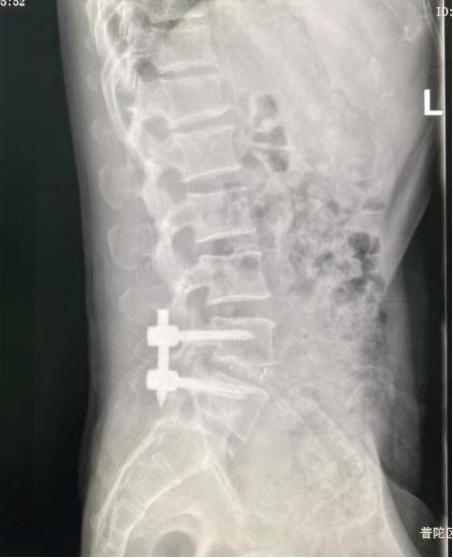

术后复查,内固定位置良好随着腰椎退行性疾病的发生率逐年上升,腰椎间盘突出症是临床上最常见的腰椎疾病,总体发病率在15%左右,中青年和老年人是腰椎间盘突出症的高发人群。经过系统保守治疗无效的患者往往需要手术治疗。由于大多数患者惧怕“开刀”,对微创手术需求不断增加,随着器械设备的不断改进与技术的逐渐成熟,使微创手术成为可能。张海龙主任医师所做的“微创”脊柱内镜腰椎椎间融合术(以下简称 “镜下融合”)采用的是经关节突入路镜下融合,配合熟练应用单及双通道进行微创脊柱融合的操作手术,该项新技术要求主刀医生要有丰富的临床经验和熟练的内镜下减压手术经验,配合先进的设备研发及不断地技术更新,才能被成熟应用在临床。